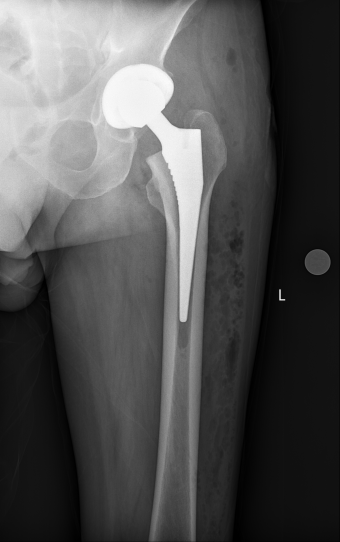

“真没想到我舅舅做了髋关节置换术后,第二天不仅能坐起来,能跷二郎腿,还能在家属的帮助下站起来走路,而且伤口只有8厘米左右,三医院骨二科的技术真的太厉害了!”骨二科患者卢大爷的外甥在卢大爷手术第二天看到他这么大的变化,兴奋惊喜之情溢于言表。这么神奇的手术效果,得益于骨二科肖聪团队采用的人工全髋关节置换手术中较为热门的微创前外侧入路(OCM入路)。

术中,肖聪团队按照术前模拟的手术方案,仅耗时1个半小时便成功为卢大爷完成了全髋关节置换手术。在骨二科医护人员细心的照料下,卢大爷术后不用再卧床,可以各方位随意“挥动”手术腿,翘起“二郎腿”,一周就康复回家。

OCM入路进行全髋关节置换术,从前方的阔筋膜张肌与臀中肌之间的间隙进入,不破坏髋关节周围肌群和后方的关节囊,实现了神经血管和肌间界面的操作。从而达到围手术期间出血量少、术后疼痛症状轻、住院时间短、髋关节脱位发生率低、患者满意度高的目标。

1.创伤切口小,切口长度一般为8-10cm;